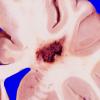

VASCULAR

Cavernous Angioma (15)